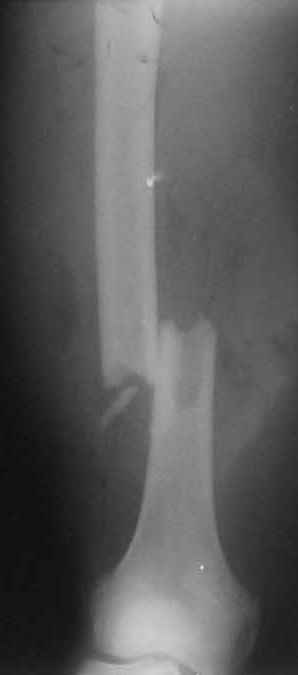

Соматически здоровый 20летний мужчина получил "высокоэнергетическое" ранение левого бедра из автомата Калашникова (5,45 мм).

Сосудисто-нервный пучок не поврежден. Традиционный подход предусматривает радикальную ПХО (расечение, иссечение и т.д.)и применение аппрата внешней фиксации. Хотелось бы услышать мнение коллег: возможен ли в данном случае нетрадиционный подход (лаваж + срочный закрытый интрамедуллярный остеосинтез + VAC) и насколько он обоснован?